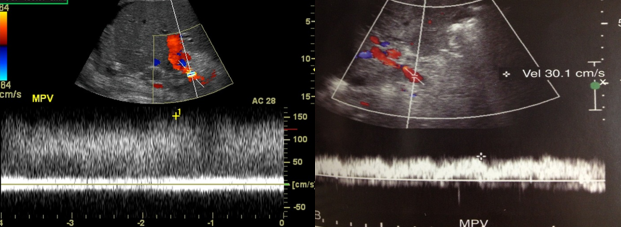

portal hypertension

portosystemic venous collaterals

portal vein occlusion

PV obstruction

portal vein thrombosis (PVT)

portal vein stenosis (PVS)